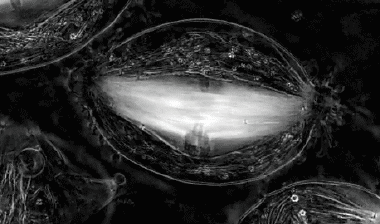

06.

T细胞的“死亡之吻”.细胞毒性T细胞(也被称为“杀手T细胞”)正在识别受病毒感染、癌变之类的“不正常细胞”,导致细胞死亡。整个动图实际用时约为75分钟。